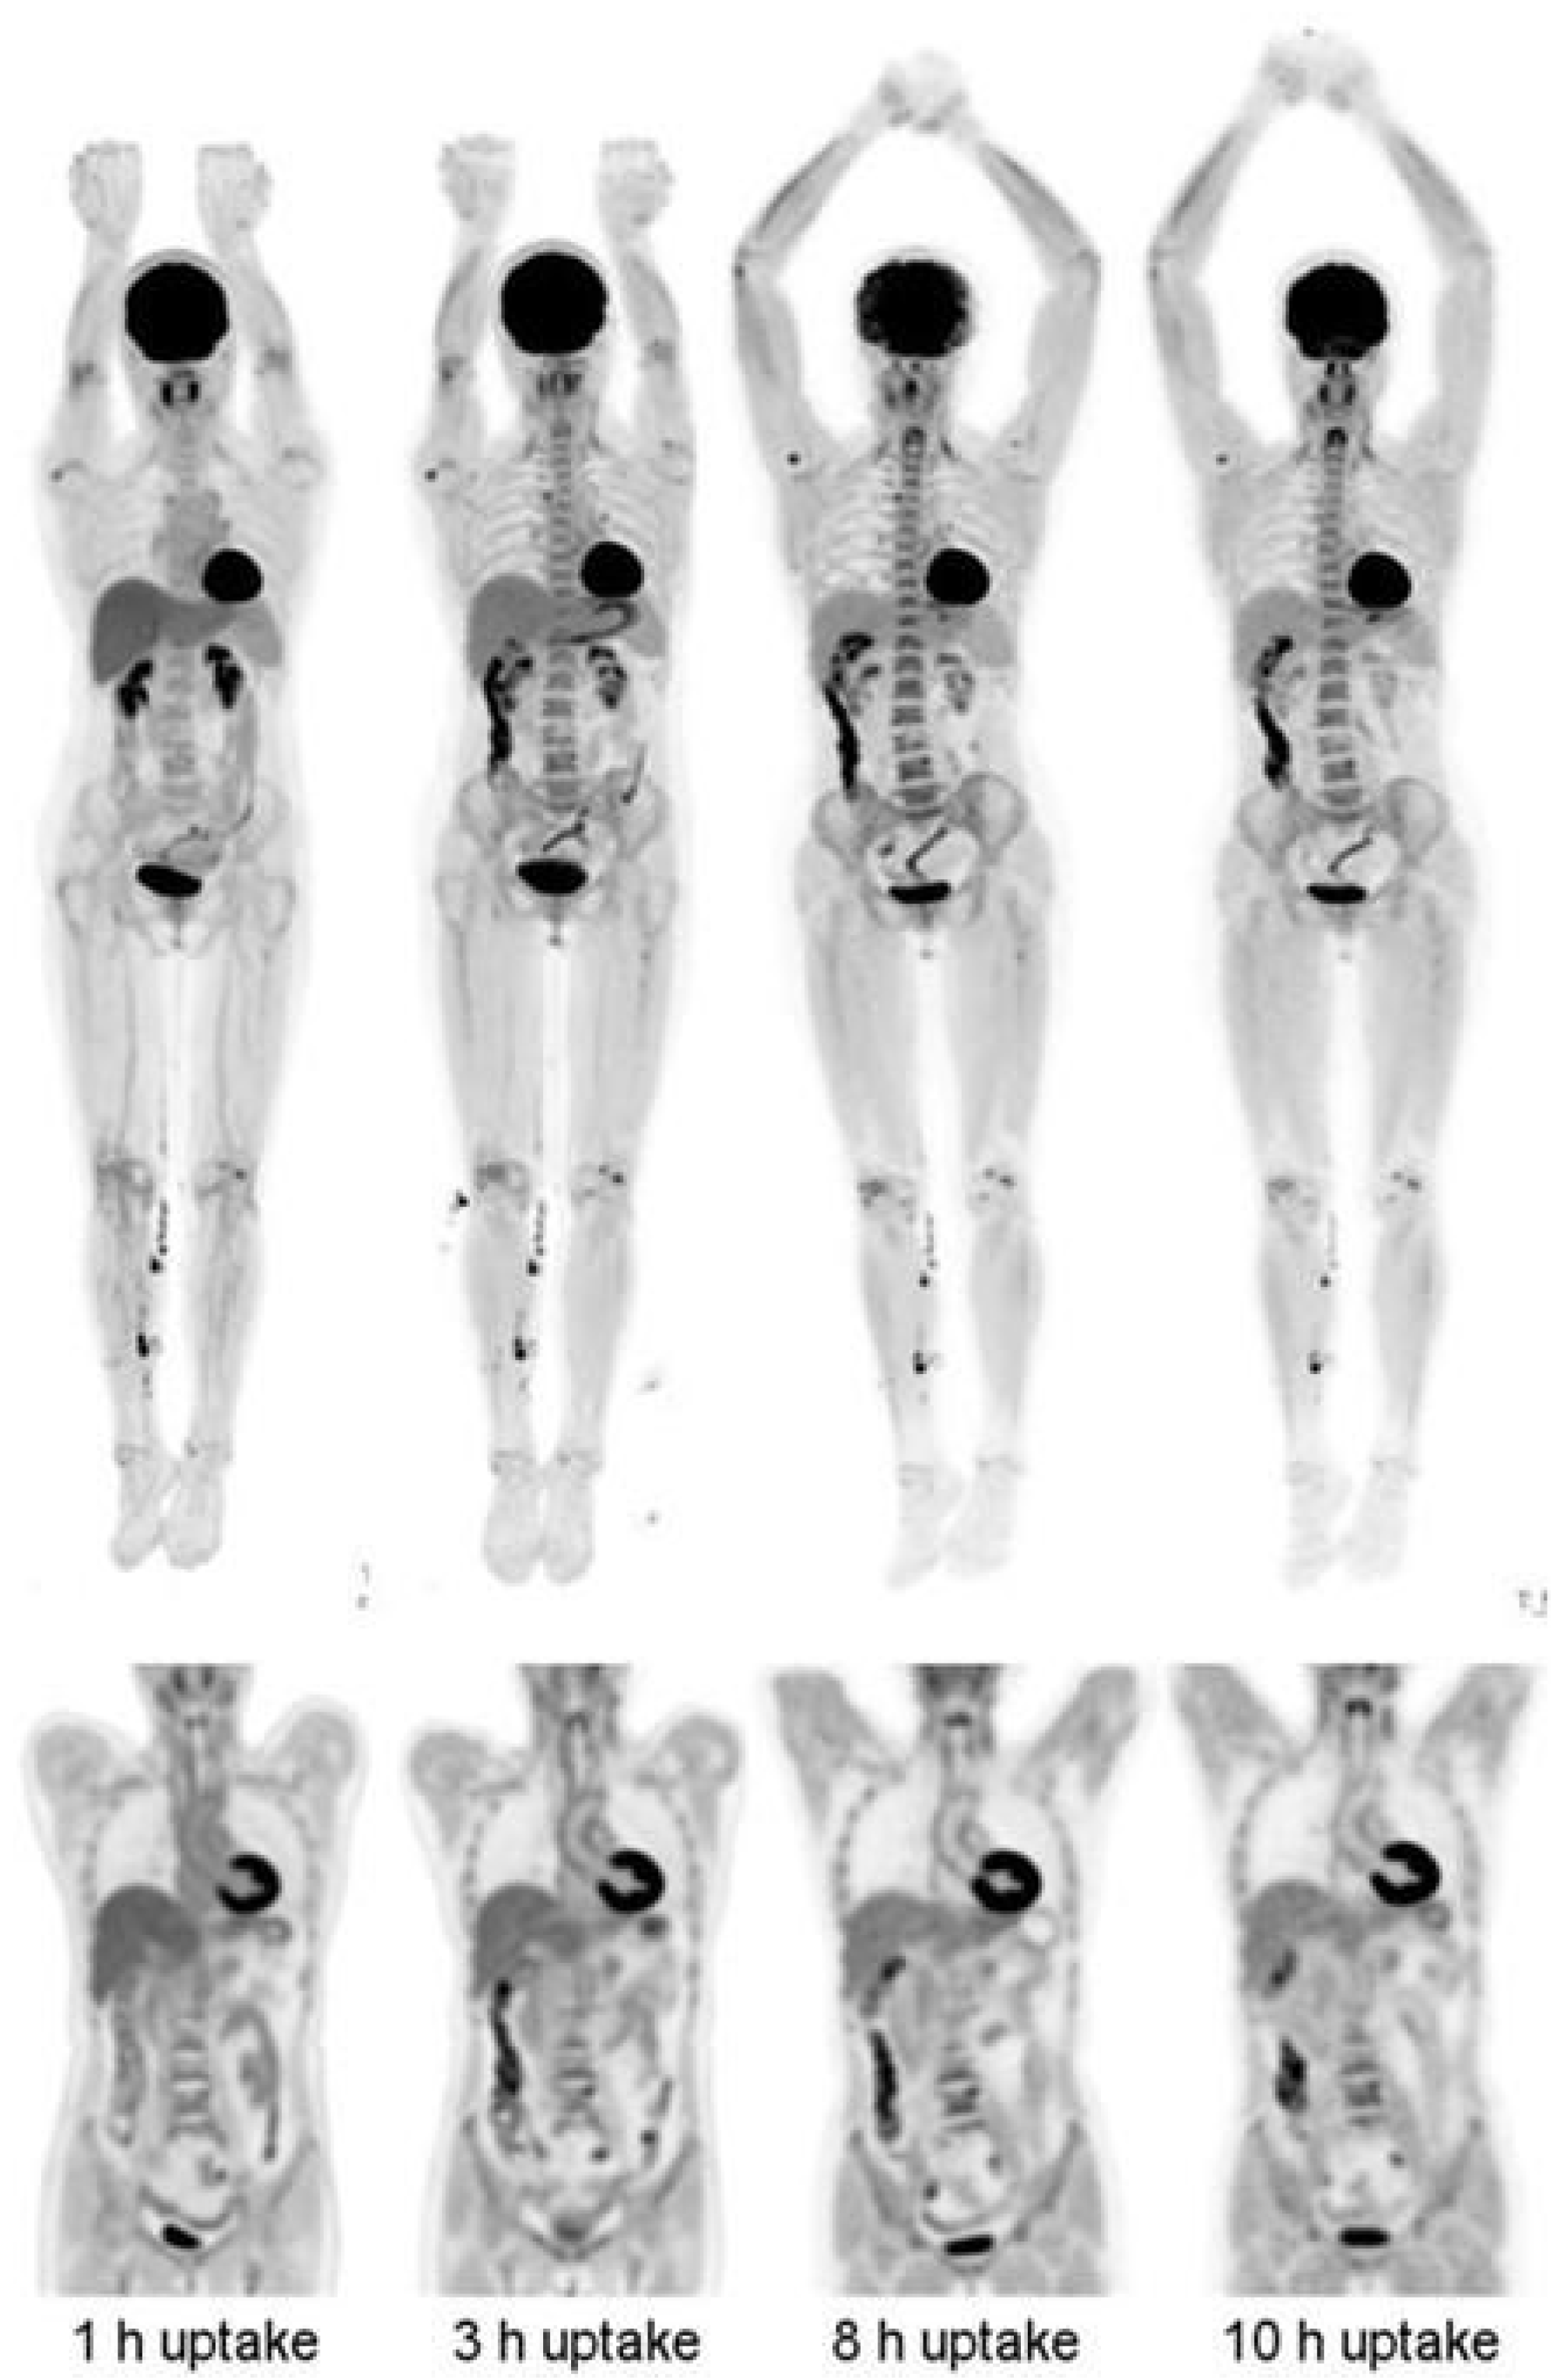

- Basu, S.; Kung, J.; Houseni, M.; Zhuang, H.; Tidmarsh, G.F.; Alavi, A. Temporal profile of fluorodeoxyglucose uptake in malignant lesions and normal organs over extended time periods in patients with lung carcinoma: Implications for its utilization in assessing malignant lesions. Q. J. Nucl. Med. Mol. Imaging 2009, 53, 9–19. [Google Scholar]

- Cheng, G.; Alavi, A.; Lim, E.; Werner, T.J.; Del Bello, C.V.; Akers, S.R. Dynamic changes of FDG uptake and clearance in normal tissues. Mol. Imaging Biol. 2013, 15, 345–352. [Google Scholar] [CrossRef]

- Houshmand, S.; Salavati, A.; Segtnan, E.A.; Grupe, P.; Hoilund-Carlsen, P.F.; Alavi, A. Dual-time-point Imaging and Delayed-time-point Fluorodeoxyglucose-PET/Computed Tomography Imaging in Various Clinical Settings. PET Clin. 2016, 11, 65–84. [Google Scholar] [CrossRef]